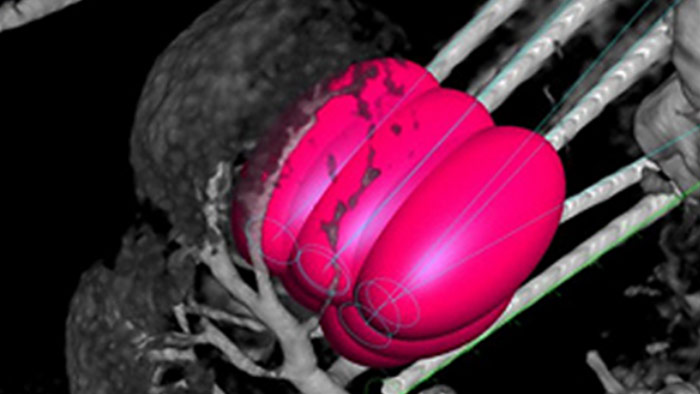

XperGuide Ablation* bietet umfassende Unterstützung bei der Behandlungsplanung und Echtzeit-Nadelnavigation. Die spezielle Parallaxenkorrektur ermöglicht die Planung von Nadelverläufen bei außermittigen Läsionen.1 Um eine möglichst gute Nadelposition für eine wirksame Ablation zu erreichen, zeigt dieses Tool den virtuellen Nadelverlauf an. Auch die Planung mehrerer Ablationsnadeln wird dadurch unterstützt. Außerdem werden Nadeleigenschaften wie Ablationszone/Isotherm angezeigt, damit die vollständige Tumorabdeckung vor der Ablation verifiziert werden kann.

Die perkutane Ablation (Hochfrequenz-, Mikrowellen- und Kryoablation) ist eine etablierte, minimal-invasive Behandlungsmethode für Nieren-, Leber-, Lungen- und Knochentumore. Dabei ist es besonders wichtig, den Tumor abzugrenzen und eine geeignete Anzahl an Nadeln und notwendigen Nadelverläufen festzulegen, damit der gesamte Tumor behandelt werden kann, ohne das umliegende Gewebe zu schädigen. Durch die präzise Navigation zur relevanten Läsion bei niedriger Strahlendosis und ohne Neupositionierung der Nadel werden die Erfolgschancen erhöht und das Komplikationsrisiko bei Biopsien und Ablationen reduziert. Der Endpunkt der Ablationsbehandlung kann mittels 3D-Bildgebung verifiziert werden, während sich der Patient noch auf dem Tisch befindet.